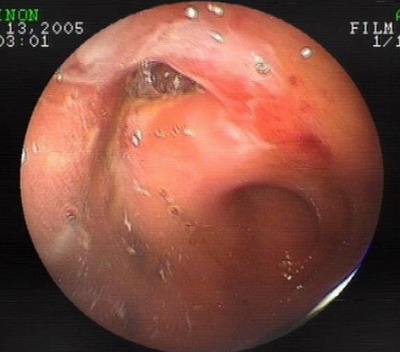

为了进一步明确诊断经口麻醉下行双气囊电子小肠镜检查:未发现病变

经肛门进镜:回肠中上段Meckel憩室伴溃疡形成。

A

双气囊电子小肠镜照片

内镜